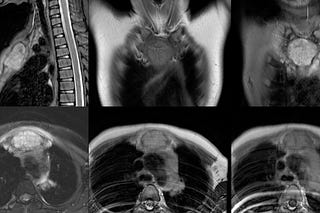

Case of the Day 100 - 2025 09 10 - T2 Dark Thoracic Spinal Vertebral Lesion - Diagnosis?

37-years old with radiating upper dorsal pain.